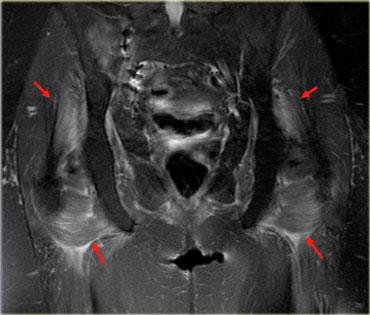

Hình bên trái là một ví dụ, lưu ý các thay đổi viêm ở các cơ lớn vùng mông.

Sau khi ngừng thuốc, đau cơ sẽ biến mất trong khoảng 2 tuần, tuy nhiên MRI vẫn còn cho thấy bất thường cho đến khoảng một tháng sau đó.

Thời điểm tốt nhất để chụp MRI theo dõi là khoảng 6 tuần sau khi ngừng thuốc.

Đây là bệnh nhân cao tuổi có tăng cholesterol máu được chỉ định dùng Lipitor.

Bệnh nhân xuất hiện đau nhức cơ, CPK tăng nhẹ.

Các thay đổi khá tinh tế, chúng ta thấy các ổ tụ dịch quanh mạc cơ, ở rìa ngoài của cơ (ngoại mạc cơ).

Ngoài ra còn có thay đổi da tối thiểu.